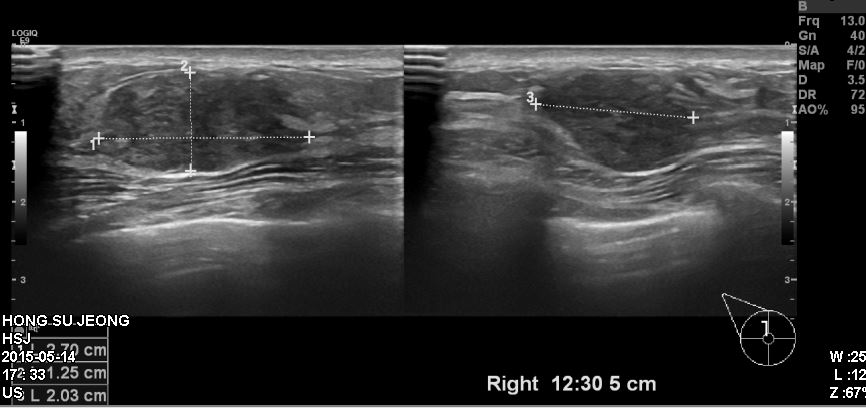

우측 유방에 만저지는 몽우리로 내원하신 50대 여성 분으로 12시 30분 방향에서

5cm 떨어진 거리에 있는 혹 조직검사 시행하여 우측 침윤성 유관암 진단

되었습니다.